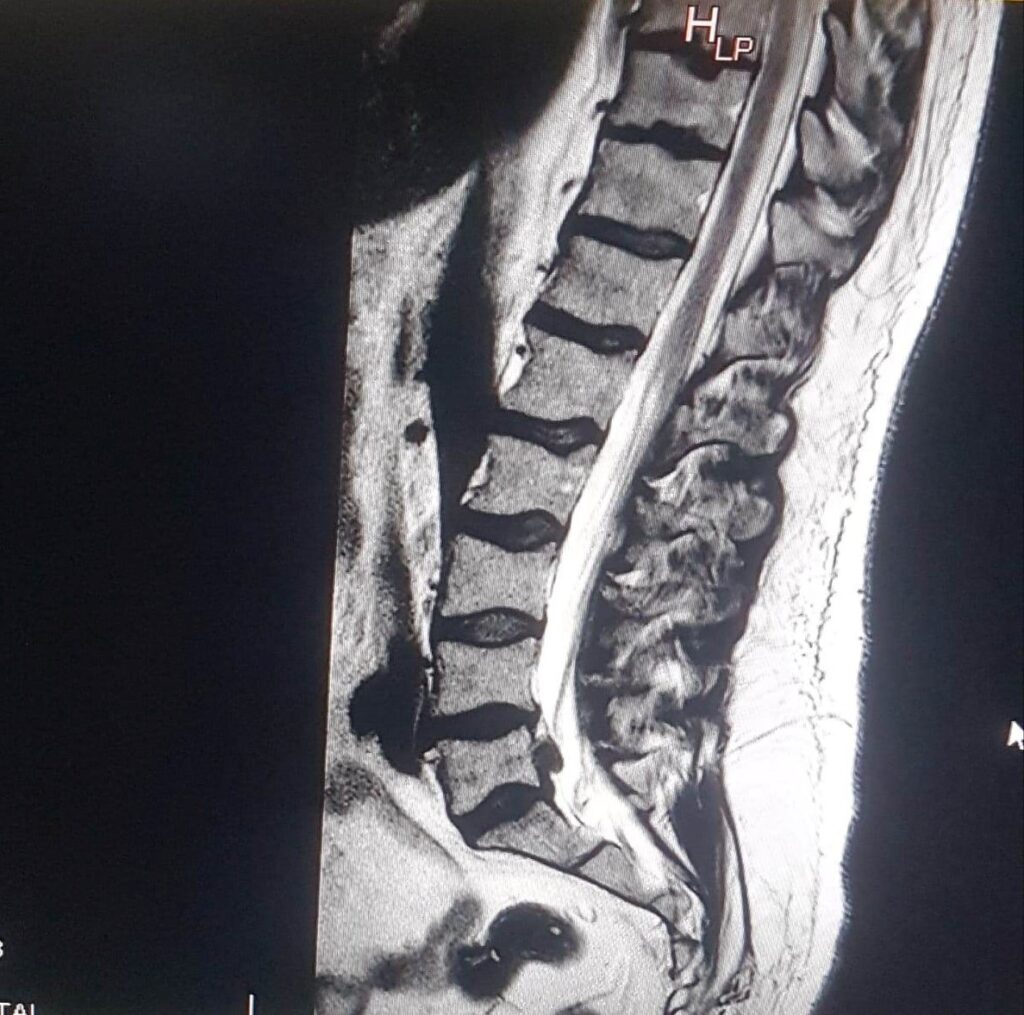

W obrazie rezonansu magnetycznego pojawiła się struktura która dawała wyżej wymienione objawy bolesności u Pacjenta.

Na dowód tego Pacjent po pół roku od pierwszego rezonansu wykonał powtórnie badanie.

W obrazie nie były widoczne żadne zmiany.